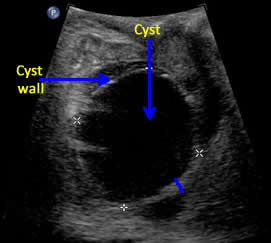

Above. Ovarian cyst. Case 1. 35 weeks gestation. The cyst wall is layered and somewhat thickened and complex. Ovarian cyst diagnosis was confirmed after birth.